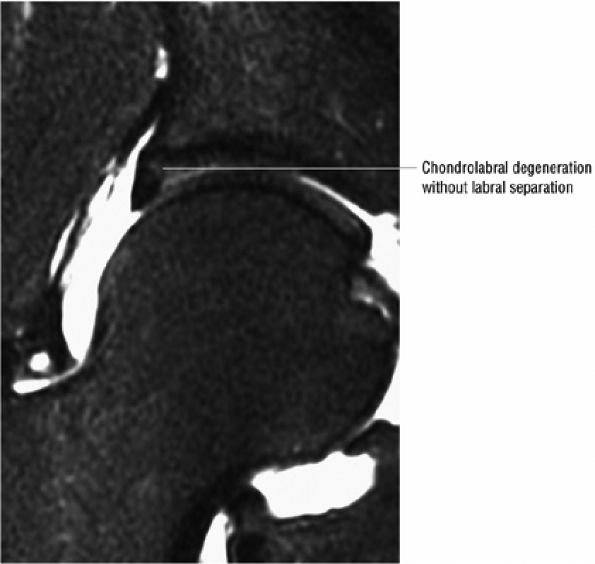

|

FIGURE 3.153 ● Gluteus medius tendinosis with intermediate-signal-intensity degeneration within the normally hypointense tendon. Sagittal PD-weighted image.

![]() |

FIGURE 3.154 ● Tendinosis of gluteus minimus associated with subgluteus minimus bursitis. Coronal FS PD FSE image.

FIGURE 3.155 ● (A) Axial FS PD FSE image showing a partial tear of the posterior gluteus medius in comparison to a full-thickness fluid-filled tendinous defect in the anterior gluteus minimus. (B) Posterolateral coronal color illustration of a partial gluteus medius tendon tear.